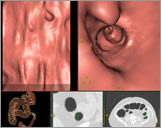

Šta je CT kolonografija?

CT kolonografija ili virtualna kolonoskopija je procedura koja koristi viseslojni CT za pregled debelog crijeva na prisustvo karcinoma ili prekanceroznih polipa. Njome se mogu otkriti tumori, polipi, krvarenje, upalne bolesti crijeva te divertikuloza.